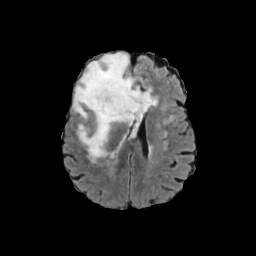

Refer to caption

CT

Zoomed

MRI

Target\mathrm{Target}

StolenEPD{\mathrm{Stolen}}^{\mathrm{D}}_{\mathrm{EP}}

StolenEPD1{\mathrm{Stolen}}^{\mathrm{D1}}_{\mathrm{EP}}

StolenITD{\mathrm{Stolen}}^{\mathrm{D}}_{\mathrm{IT}}

StolenITD1{\mathrm{Stolen}}^{\mathrm{D1}}_{\mathrm{IT}}

Figure 7: Lossy image reconstructions on CT (row 1, 2) and MRI (row 3, 4) images, where the row 2, 4 provide a zoomed-in view of the bounding box region of the row 1, 3. The leftmost column represents the target images, while the subsequent four columns show the stolen images reconstructed by the decoder D or D1 in two scenarios.

A visual comparison between target and stolen images is available in Fig. 7. We observe that the stolen images from IT Scenario closely resemble the input ones, particularly in the tumor regions, whereas stolen images from EP Scenario exhibit blurring artifacts in finer details. In both cases, the stolen images reconstructed by D1D1 demonstrate a comparable quality to those reconstructed by DD, thus further confirming the effectiveness of the reduced decoder D1D1.